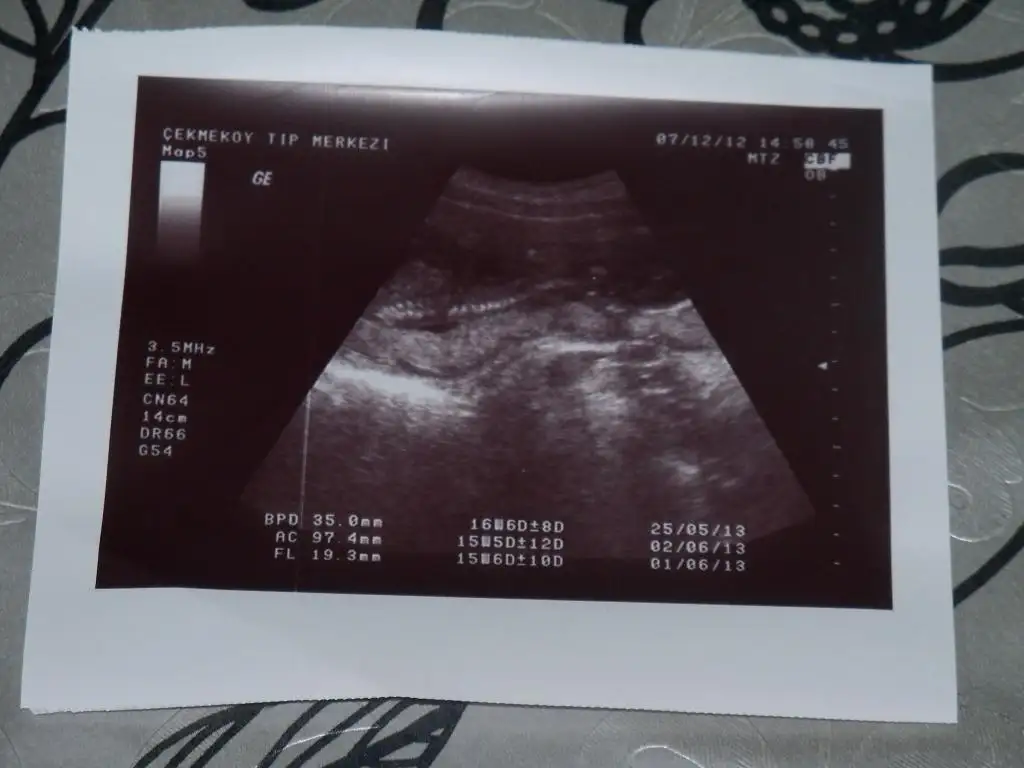

Çok sağol canım kızı kesin gördük bizde evde evirip çevirip bakıyoruz ama erkeğe emin olamadık, sana güveniyorum bu konuda,idrar testimide sen yorumlamıştın hayırlısı olsun bakalım dr hiçbir tahmin yapmadı 16. hafta diyor.

17.haftaya geldik hala kesin değil bizim sıpanın cinsiyeti :) bir de sizden yorum almak isterimmmm :)

Eki Görüntüle 574480 Eki Görüntüle 574481 Eki Görüntüle 574482